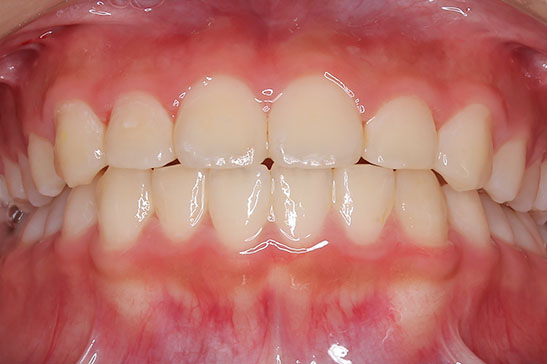

側方歯(犬歯、小臼歯)の生え変わりの時期。 前歯のがたつきを気にされ、小児矯正からの治療を希望されました。 お母様は、矯正治療経験済みですので、治療には前向きで早期治療の必要性を納得されていました。 小児矯正では、永久歯の生え変わるためのスペースを増加させ、がたつきを軽減させることを目的で行います。 残ったがたつきは、全ての永久歯が生え変わってから、本格矯正(マルチブラケット装置での治療)で改善しています。 比較的、叢生量は少ないため、本格矯正は非抜歯にて配列しました。

マルチブラケット 動的治療期間 2年6か月 調整回数16回 特に問題もなく、保定後も安定しています。